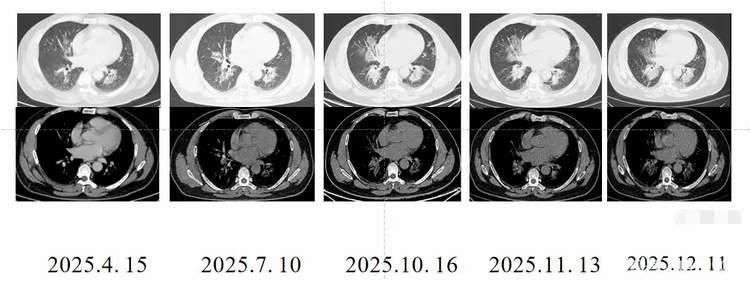

去年四月,装修工老王感冒后出现了胸闷、咳嗽、咳痰的症状,去当地医院就诊。检查显示其双肺有渗出性病变,无法排除肿瘤、肺炎的可能,随即转往了河南省人民医院。河南省人民医院经过系统检查,发现老王体内有肺炎链球菌等病菌,对症抗感染治疗后,胸闷症状仍未缓解,病因成谜。就在医生准备进一步排查时,老王坚持要出院。医生建议老王每隔一两个月复诊一次,但老王并不当回事儿,一拖就是八个多月。期间,河南省人民医院老年医学科主治医师刘雪亚反复提醒老王尽快住院,继续治疗。但老王一直不在意,直到最近胸闷明显加重,他才再次来到医院就诊。经CT引导下肺穿刺活检,医生最终确诊老王患的是罕见病——肺泡蛋白沉积症。

刘雪亚介绍说,肺泡蛋白沉积症就像“肺泡里灌了牛奶糊”一样,是由先天性或继发性因素引起肺表面活性物清除障碍或产生异常,导致大量脂蛋白沉积在肺泡腔和肺泡巨噬细胞的一种罕见呼吸病。该病年发病率约0.36/10万,极为罕见,并且近1/3患者早期无任何症状,容易导致误诊或漏诊。确诊后,老王才知道这种病治疗难度大,极端情况下甚至需要肺移植!万幸的是他的病情还没发展到该阶段。医生采用雾化联合全肺灌洗术的治疗方案,用了三个多小时,才把老王肺泡里的“牛奶糊”样物质清理干净,目前老王正在康复中。